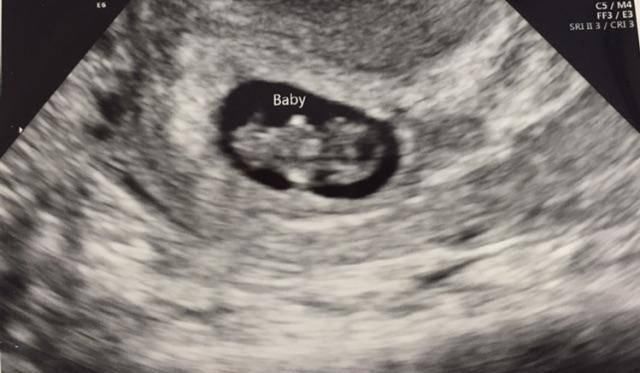

B超检查

第一次产检做B超是最重要的,这项检查可以看到胎儿的发育情况,孕妈妈可以选择阴超也可以选择腹部B超。

阴超更适合再早一些的检查,或者检查子宫内肌瘤。对于阴超,很多妈妈有顾虑,怕流产,所以选择的很少。但实际上是安全的,如果要确定更复杂的情况可以选择阴超。

大部分孕妈妈会选择腹部B超,腹部B超最大的问题是要憋尿。因为这时候胚胎很小,被膀胱遮挡看不清楚。喝水憋尿后,使膀胱充盈,赶走气体,子宫才能正常显影。

本次检查主要看孕囊、胎心和胎芽。